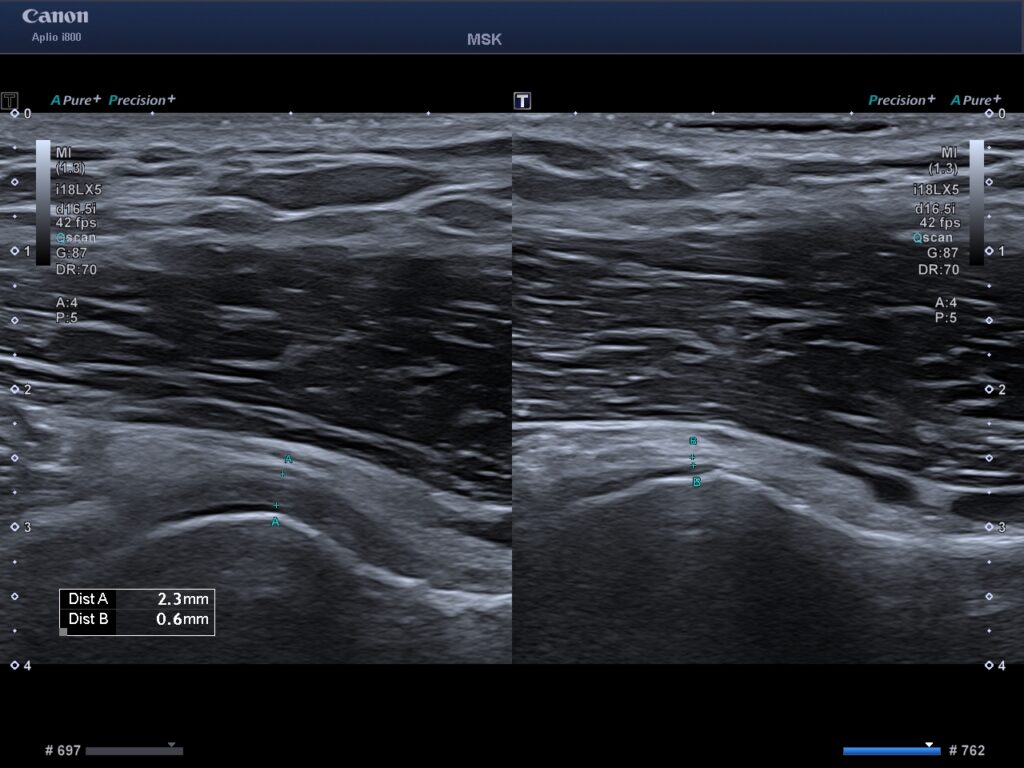

Till vänster ses aktivitet i ett ligament som normalt inte ska finnas där. Detta är ett tecken på en frozen shoulder vid ultraljudsundersökning.